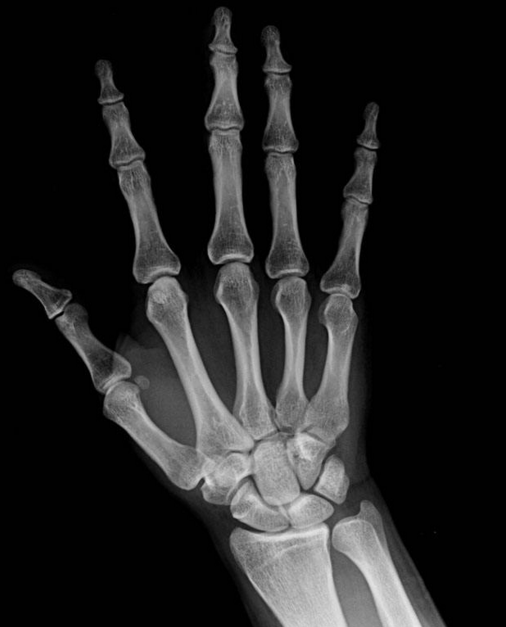

灰度的概念晦涩难懂,但是它的应用在生活中却不鲜见,在医学、图像识别领域有很广泛的用途。比如我们在医院体检时拍摄的CT(电子计算机断层扫描)、MR(磁共振检查)、B超、X光都是灰度图像,以灰阶即亮度模式的形式来诊断病症。